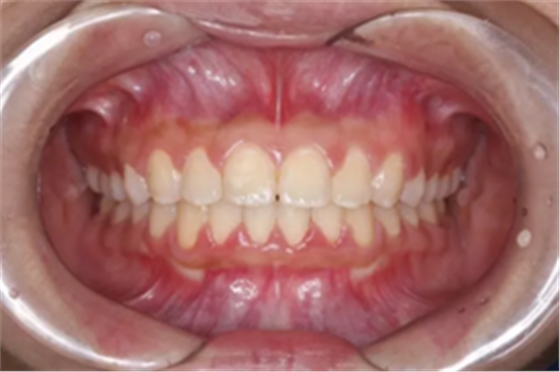

但前牙閉鎖合是上前牙下垂伸長,內(nèi)扣完全鎖住了下切牙,正面觀時我們常看不到下切牙,下切牙則常擁擠伸長咬到了上腭內(nèi)的牙齦上,上下前牙發(fā)生的交角幾近180°。

前牙閉鎖合-深覆合

前牙閉鎖合覆蓋